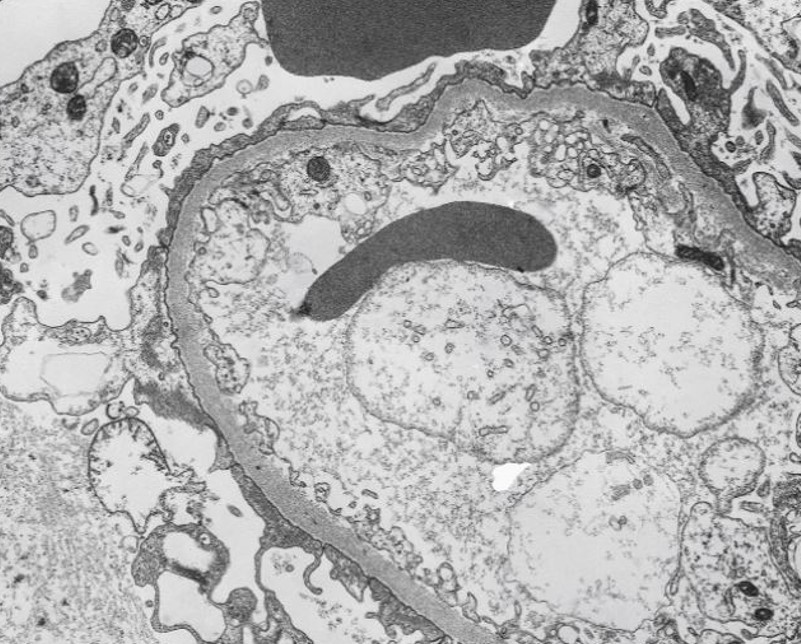

What is this and why?

Minimal Change Disease - podocyte foot process effacement